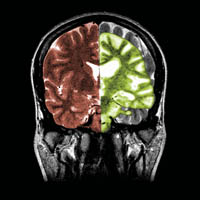

composite MRI image

A composite image showing a normal coronal (frontal) cross-sectional MRI image of the brain (in brown) with a superimposed coronal MRI image of a brain with advanced Alzheimer's disease (in green). The diseased brain shows severe generalised atrophy (shrinkage) of brain tissue with an accentuated loss of tissue involving the temporal lobes